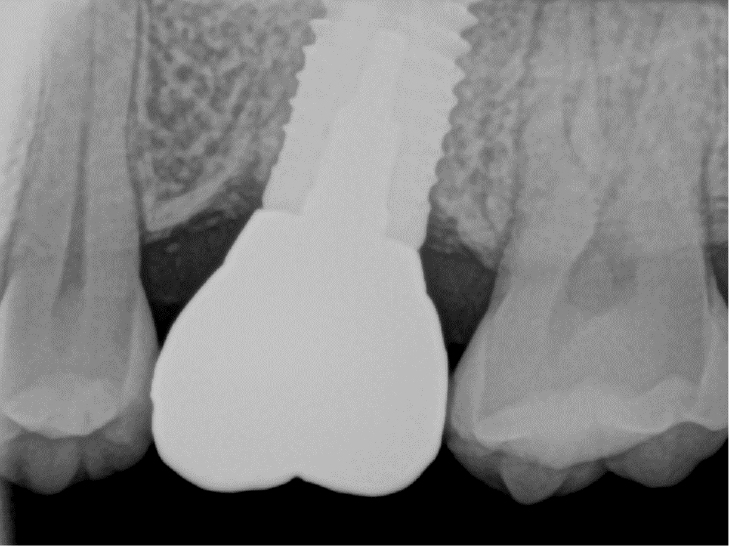

At the next visit, the cast post was tried in (Fig. 5B), and the internal and marginal fits were checked clinically and radiologically (Fig. 6). The cast post was passively fit into the fixture, and the margin was set with an equigingival finish line. The upper prosthesis was made of a monolithic zirconia using the computer-aided design/computer-aided manufacturing (CAD-CAM) technique. The master cast was scanned with a model scanner (T500; Medit, Seoul, Korea), and the monolithic restorations were designed digitally, with narrow occlusal table width and minimal cusp inclination to minimize the offset load.

After adjustment, the inner side of the fixture was rinsed with chlorohexidine and normal saline and dried using absorbent paper points (ProTaper Gold Absorbent Point; Dentsply Sirona). The cast post was bonded to the fixture with a resin-based cement (PANAVIA™ F 2.0; Kuraray Noritake Dental, Tokyo, Japan). Cement was applied to the post, and the post was seated in the post space with finger pressure. Excess cement was removed, and periapical radiographs were taken to check whether the cement had remained or not. The zirconia prosthesis was cemented with a resin-modified glass ionomer cement (FujiCEM® 2; GC Corporation, Tokyo, Japan) (Fig. 7).

Precautions after implant prosthesis delivery, such as avoiding hard and chewy foods, were explained to the patient. Periodic occlusion check was performed. At the 2-year follow-up, no implant complications, including detachment of the abutment or prosthesis, were observed (Fig. 8).